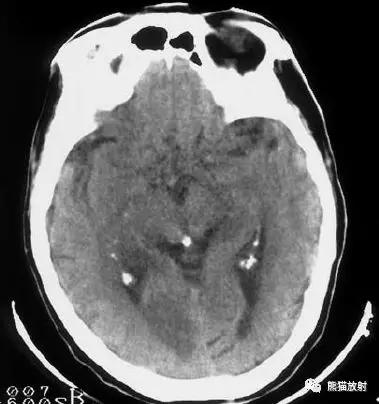

椎基底动脉区域的梗死:范围较广,非均质的低密度区域,累及脑干,小脑半球的前外侧以及颞叶的内后侧。

后颅窝梗死:脑桥、中脑、左小脑半球。

左侧及双侧丘脑梗死